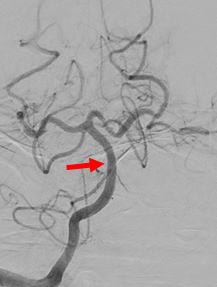

図4:Penumbra血栓吸引カテーテルと血栓除去用ステントを用いて血栓除去を行い、TICI3の完全再開通を認めました。 |